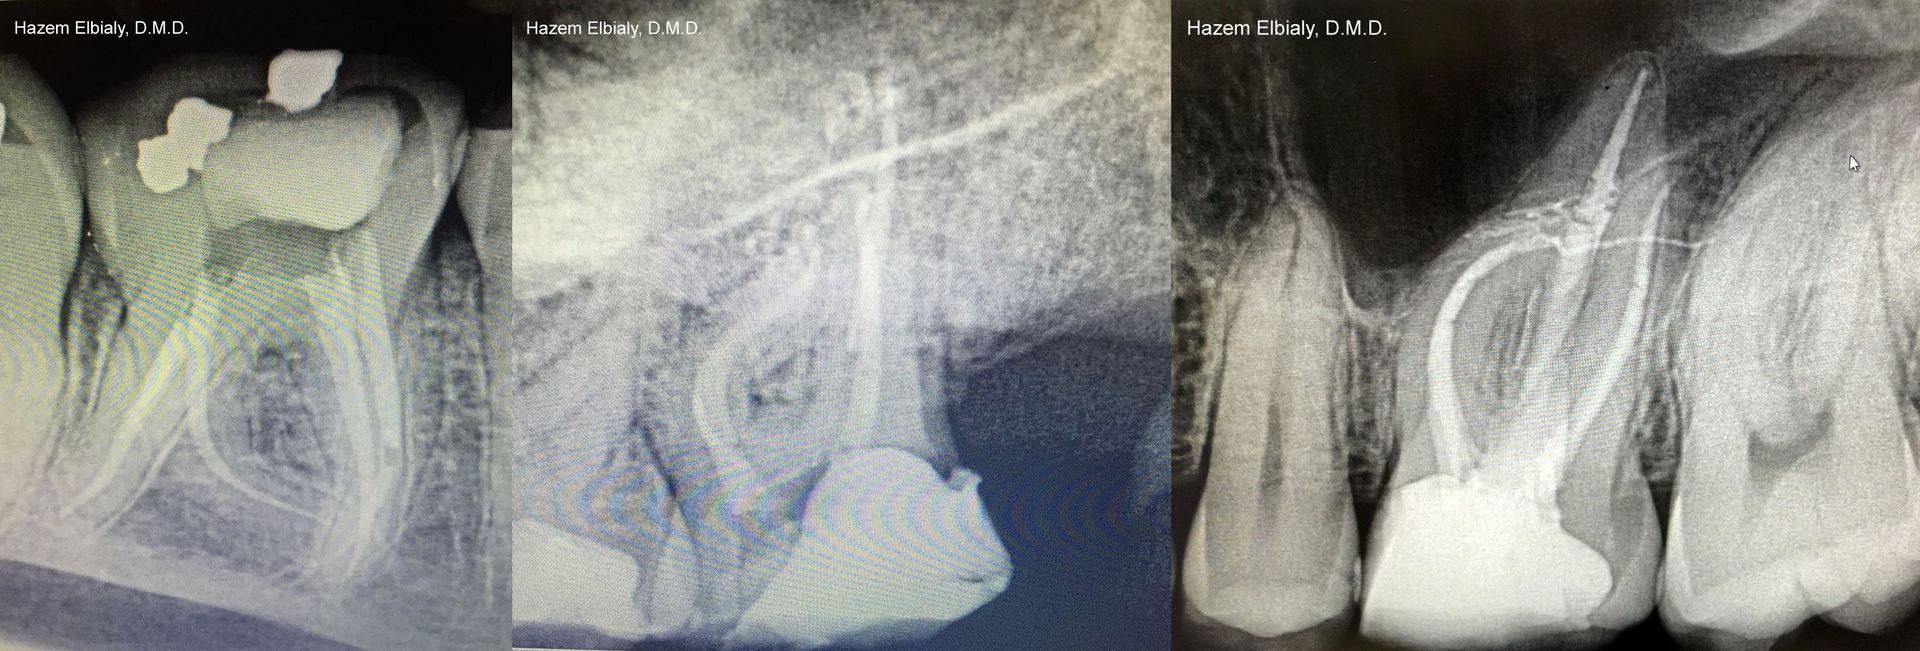

How We Do a Root Canal

Our root canals are quick and painless. Dr. Elbialy ensures you are adequately anesthetized and comfortable before beginning the procedure. He uses an electronic apex locator and NiTi instruments for speed, pinpoint precision, and accuracy.